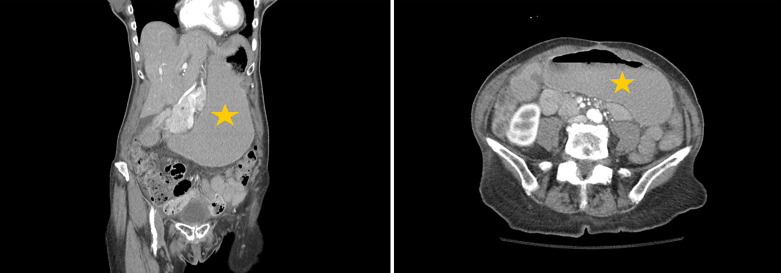

简介急性胃扩张(AGD)是由气体、胃分泌物或食物堆积引起的胃部大量膨胀。AGD 是一种放射学诊断,没有明确的发病机制,由于缺乏明确的诊断标准和医生的认识,AGD 经常被误诊:在本病例系列中,我们描述了 4 位 AGD 患者的临床表现和治疗结果。其中三名(75%)患者为女性,一名(25%)患者为男性。患者年龄从 53 岁到 84 岁不等,平均年龄为 73.5 岁。腹痛、恶心和呕吐是最常见的主诉。两名患者(50%)患有癌症,一名患者(25%)患有后天性十二指肠狭窄,第四名患者出现回肠梗阻:AGD是一种外科急症,死亡率高达50%-100%;因此,及时诊断和治疗至关重要。在此,我们描述了本院诊断和处理的一系列 AGD 病例。我们旨在提高人们对这一致命但未得到充分认识的临床实体的认识。

Introduction: Acute gastric dilatation (AGD) is a massive distension of the stomach caused by the accumulation of gas, gastric secretions, or food material. AGD is a radiological diagnosis with no clear etiopathogenesis and is often misdiagnosed owing to a lack of clear diagnostic criteria and physician awareness.

Case presentation: In this case series, we describe the clinical presentations and outcomes of 4 patients with AGD. Three (75%) of the patients were female, and one (25%) was male. The patients' ages ranged from 53 to 84 years, with an average age of 73.5 years. Abdominal pain, nausea, and vomiting were the most frequently reported complaints. Two (50%) patients had cancer, one (25%) had an acquired duodenal stenosis, and the fourth patient experienced an ileus.